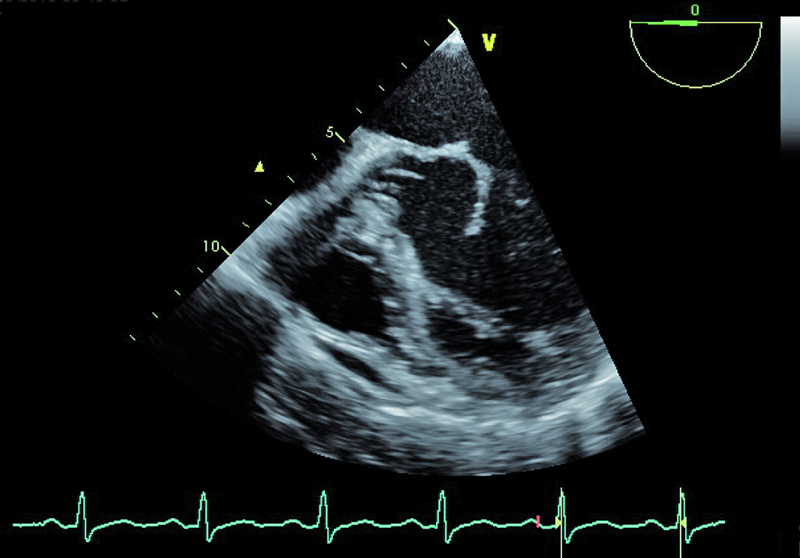

Infekcyjne zapalenie wsierdzia z zajęciem obu natywnych zastawek serca lewego nie budzi w tym przypadku wątpliwości. Proces zapalny może być rozpoznany echokardiograficznie na podstawie linijnych ech mogących odpowiadać rozerwanemu płatkowi zastawki aortalnej oraz na podstawie ciężkiego wypadania płatka zastawki mitralnej (flail), mającego zapewne charakter poinfekcyjny (ryc. 1). Stopień destrukcji zastawki mitralnej w porównaniu z zastawką aortalną wydaje się większy. Między segmentami A2 i P3 pojawia się tętniakowate uwypuklenie, będące pozostałością nacieczenia zapalnego i martwicy tkanki (ryc. 2). Tryb kolorowego doplera ujawnia dwa strumienie niedomykalności – jeden, ekscentryczny wynikający z wypadania przedniego płatka i biegnący wzdłuż bocznej ściany przedsionka (ryc. 3), i drugi pojawiający się w pewnej odległości od miejsca koaptacji, w miejscu, w którym fali zwrotnej trudno się spodziewać, jeśli struktura tkanki budującej płatek jest nienaruszona (ryc. 3, 4). Strumień niedomykalności mitralnej ma w tym wypadku charakter ostry i trafia do nieprzygotowanej i niepowiększonej jamy lewego przedsionka (ryc. 3, 4). Umiarkowana dotychczas niedomykalność aortalna, którą chory przez wiele lat dobrze tolerował, się nasiliła. Dowodem na to jest krótki czas spadku gradientu ciśnień aorta – lewa komora (poniżej 200 ms) (ryc. 5) oraz wyraźny sygnał wsteczny holodiastoliczny w aorcie zstępującej, świadczący o wysokiej wartości frakcji niedomykalności aortalnej (iloraz całki prędkości wypływu krwi na obwód i prędkości fali wstecznej 83%!) (ryc. 6).